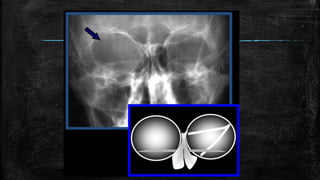

Ice-cream cone” sign of vestibular

schwannoma

• #64 Ice-cream cone” sign of vestibular schwannoma. (a) Axial T1 SPGR post-contrast image shows an avidly enhancing mass (white solid arrow) extending from the CPA to the fundus of the IAC. (b) When large enough, vestibular schwannomas viewed in the axial plane resemble an “ice-cream cone” with the bulbous extension of tumour in the CPA resembling the ice-cream sitting upon a cone of tumour in the IAC.

• #65 “Broken Heart” and “Y” signs of incudomalleolar disarticulation. (a) Coronal non-contrast enhanced CT shows widening of the incudomalleolar joint (white solid arrow) with lateral displacement of the short process of the incus (white open arrow) relative to the head of the malleus (white arrowhead). (b) This configuration of the ossicles observed on coronal CT has been likened to the appearance of a “broken heart” or “Y”.

• #66 Corkscrew cochlea” sign of X-linked stapes gusher. (a) Axial non-contrast CT of the temporal bones demonstrates an abnormal morphology of the cochlea (white solid arrow) with absent interscalar septum and modiolus, as well as a bulbous configuration of the lateral internal auditory canal (white open arrow). (b) This abnormal cochlear configuration resembles a corkscrew and is typical of X-linked stapes gusher.